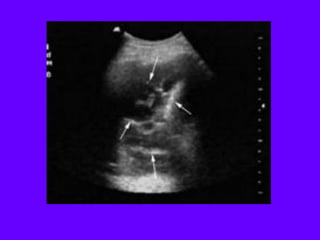

Tissue pattern representative of Alveolar

Consolidation

Presence of hyperechoic punctiform

imagesrepresentative of air bronchograms

Pleural

effusion

Lower lobe

Tissue pattern representativeof Alveolar Consolidation Presence of hyperechoic punctiform imagesrepresentative of air bronchograms Pleural effusion Lower lobe